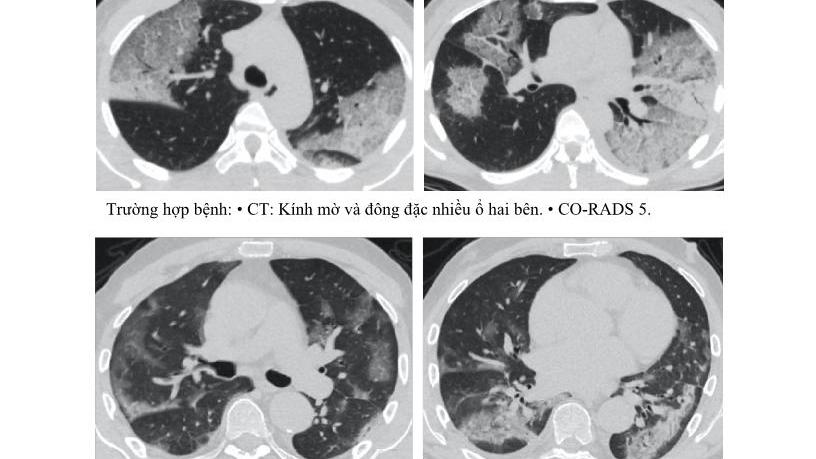

Không chỉ ‘thích’ phổi, virus corona mới còn tấn công hàng loạt nội tạng

Càng ngày càng có thêm nhiều dữ liệu cho thấy virus nCoV nguy hiểm ngoài tầm hiểu biết của các nhà khoa học khi gây ra hàng loạt tổn thương.